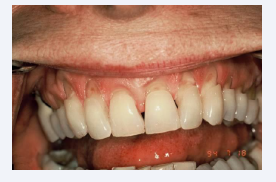

Deformations of Restorative Materials

Fatigue easily manifests itself in prostheses and restorative materials such as amalgam and acrylic. Termed Luder Lines or molecular slip bands, the molecules in the alloy are rearranging themselves under the influence of compressive strain (Figures 5 and 6). One can demonstrate the effect by bending a metal coat hanger back and forth and examining the stress configuration that is produced [8].

Figure 5 Deformations in acrylic

Figure 5: Deformations in acrylic

Figure 6 Deformations in acrylic

Figure 6: Deformations in acrylic

Fatigue in Acrylic appears as wavy lines or sets (Figures 7 and 8).